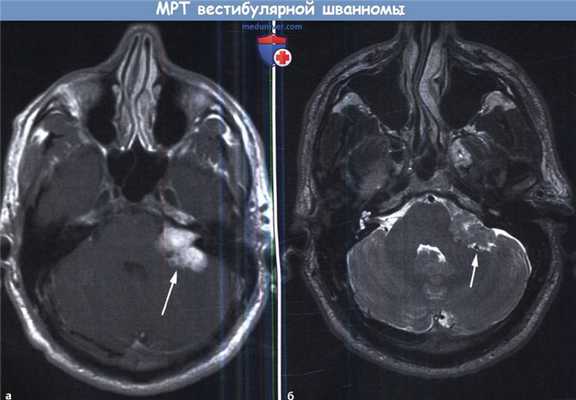

Оптимальными способами визуальной диагностики являются компьютерная томография (КТ) и магнитно-резонансная томография (МРТ) головного мозга. Эти исследования принято проводить с контрастным усилением, так как оно позволяет обнаружить даже небольшие новообразования [14] . Иногда опухоль обнаруживается случайно — при проведении КТ или МРТ головного мозга по другому поводу [13] . По результатам этих исследований можно поставить точный диагноз, выявить локализацию опухоли, её размеры, структуру, отношение к окружающим тканям задней черепной ямки, спланировать тактику хирургического или радиологического лечения [12] .